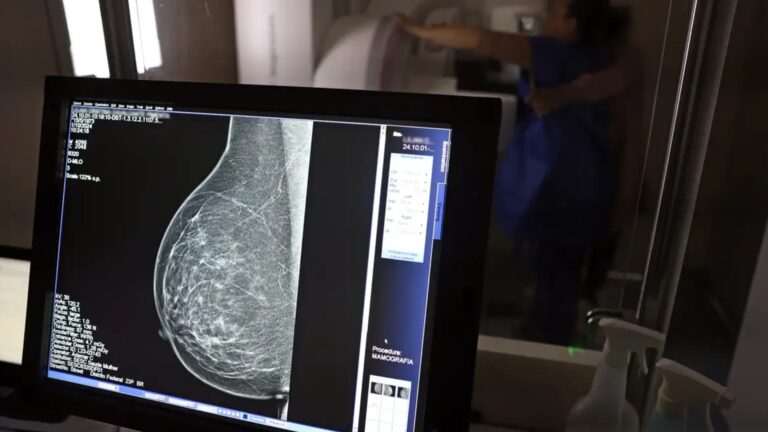

O Ministério da Saúde passou a recomendar o acesso a mamografia, via Sistema Único de Saúde (SUS), para mulheres de 40 a 49 anos – mesmo que não haja sinais ou sintomas de câncer de mama. De acordo com a pasta, a faixa etária concentra 23% dos casos da doença, e a detecção precoce aumenta as chances de cura.

Até então, a orientação era que o exame fosse feito a partir dos 50 anos.

A medida faz parte de um conjunto de ações anunciadas nesta terça-feira (23) voltado para a melhoria do diagnóstico e da assistência. A recomendação para mulheres a partir dos 40 anos é que o exame seja feito sob demanda, em decisão conjunta com o profissional de saúde.

As mamografias via SUS em pacientes com menos de 50 anos, de acordo com a pasta, representam 30% do total, o equivalente a mais de 1 milhão apenas no ano de 2024.

Outra medida anunciada é a ampliação da faixa etária para o rastreamento ativo – quando a mamografia é solicitada de forma preventiva a cada dois anos. A idade limite, até então, era 69 anos. Agora, passa a ser 74 anos. Dados do ministério revelam que quase 60% dos casos de câncer de mama estão concentrados entre 50 e 74 anos.

“A ampliação do acesso à mamografia aproxima o Brasil de práticas internacionais, como as adotadas na Austrália, e reforça o compromisso em garantir diagnóstico precoce e cuidado integral às mulheres brasileiras. O câncer de mama é o mais comum e o que mais mata mulheres, com 37 mil casos por ano”, reforçou a pasta.

Os números mostram que, em 2024, cerca de 4 milhões de mamografias para rastreamento e 376,7 mil exames diagnósticos foram realizados no SUS.